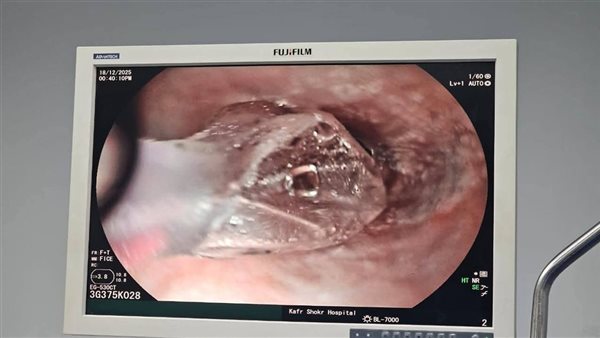

وتعود تفاصيل الحالة إلى استقبال المستشفى مريضًا يبلغ من العمر 65 عامًا، كان يعاني من صعوبة شديدة في البلع أثرت على حالته الصحية وجودة حياته اليومية، وعلى الفور، جرى توقيع الكشف الطبي اللازم وإجراء الفحوصات الدقيقة باستخدام المنظار، والتي أسفرت عن تشخيص الحالة بوجود ضيق شديد في منتصف المريء.

وقرر الفريق الطبي بعد التقييم الطبي الشامل، التدخل العلاجي باستخدام منظار المعدة وتقنية التوسيع بالبالون، حيث تم تنفيذ الإجراء وفقًا للبروتوكولات الطبية المعتمدة، مع الالتزام الكامل بمعايير السلامة ومكافحة العدوى.

وتمت العملية بنجاح كامل دون أي مضاعفات، وأسفرت عن تحسن واضح وملحوظ في حالة المريض، الذي بدأ في استعادة قدرته على البلع بشكل طبيعي.